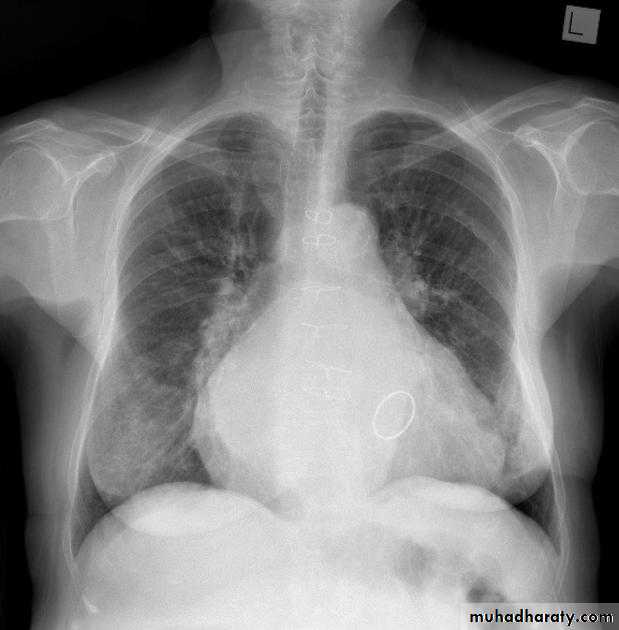

Mitral valve diseaseCXR of adult male , PA view shows: Enlargement of the cardiac shadow (cardiomegaly), Enlargement of left atrium Double density sign: the right side of the enlarged left atrium pushes into the adjacent lung and creates an addition contour superimposed over the right heart.

Mitral valve disease (double density RT cardiac border)CXR of adult , PA view shows: Cardiomegally Double density sign of right cardiac border Enlargement of left atrium, permenant left atrial appendage and relaced mitral valve (prosthesis)